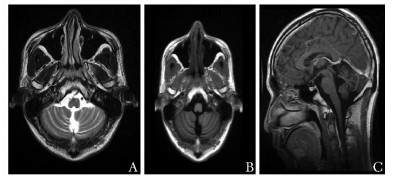

• 摘要: 亚急性小脑性共济失调多见于非典型感染、自身免疫性疾病和副肿瘤性小脑变性。本文报道1例表现为亚急性小脑性共济失调患者,其病因罕见。该患者男性,31岁,亚急性起病,临床表现为小脑性共济失调,严重免疫抑制状态,经筛查发现人类免疫缺陷病毒(human immunodeficiency virus, HIV)抗体及核酸均阳性、脑脊液JC病毒DNA阳性,临床诊断为JC病毒小脑颗粒细胞神经元病,经抗逆转录病毒治疗后共济失调症状好转, 3个月后随访症状稳定。JC病毒小脑颗粒细胞神经元病是一种JC病毒感染引起的新型临床症候,目前报道较少,本例为国内首次报道。本病例提示HIV感染免疫抑制患者出现共济失调时需筛查JC病毒,免疫功能的恢复有助于控制JC病毒小脑颗粒细胞神经元病症状进展。

Abstract: The most common etiologies of subacute cerebellar ataxia include atypical infections, autoimmune disorders, and paraneoplastic cerebellar degeneration. We reported a rare etiology of subacute cerebellar ataxia in a young man. A 31-year-old man was admitted to our hospital for subacute progressive cerebellar ataxia. He was detected HIV positive, and DNA of JC virus positive in his cerebrospinal fluid. He was diagnosed with JC virus cerebellar granule cell neuronopathy, and symptoms got improved after anti-retroviral therapy. At the 3-month follow up, his condition was stable. Cerebellar granule cell neuronopathy is a novel syndrome caused by JC virus infection. Our case indicated that JC virus infection should be considered when an immune-compromised patient with positive HIV develops cerebellar ataxia. Restoring immune function helps to control the progress of JC virus cerebellar granule neuronopathy. We summarized the diagnostic approach and treatment of subacute cerebellar ataxia through retrospectively reviewing the clinical data of the young man.